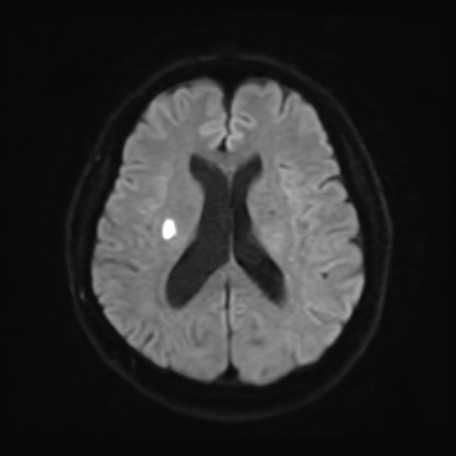

MRI検査

内科領域

頭部

脳梗塞